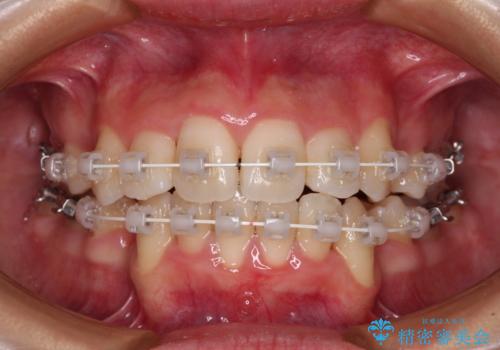

デコボコと出っ歯 抜歯矯正でスッキリとした口元に

- 上下前歯の八重歯やデコボコと、唇の閉じにくさを気にして来院された患者様です。

口元の突出感を改善するため、上下左右の第一小臼歯4本を抜歯し、ワイヤー装置にて矯正治療を行うこととしました。

デコボコの解消で歯が磨きやすくなり、抜歯矯正により口元の突出感が大幅に改善され、スッキリした口元になりました。